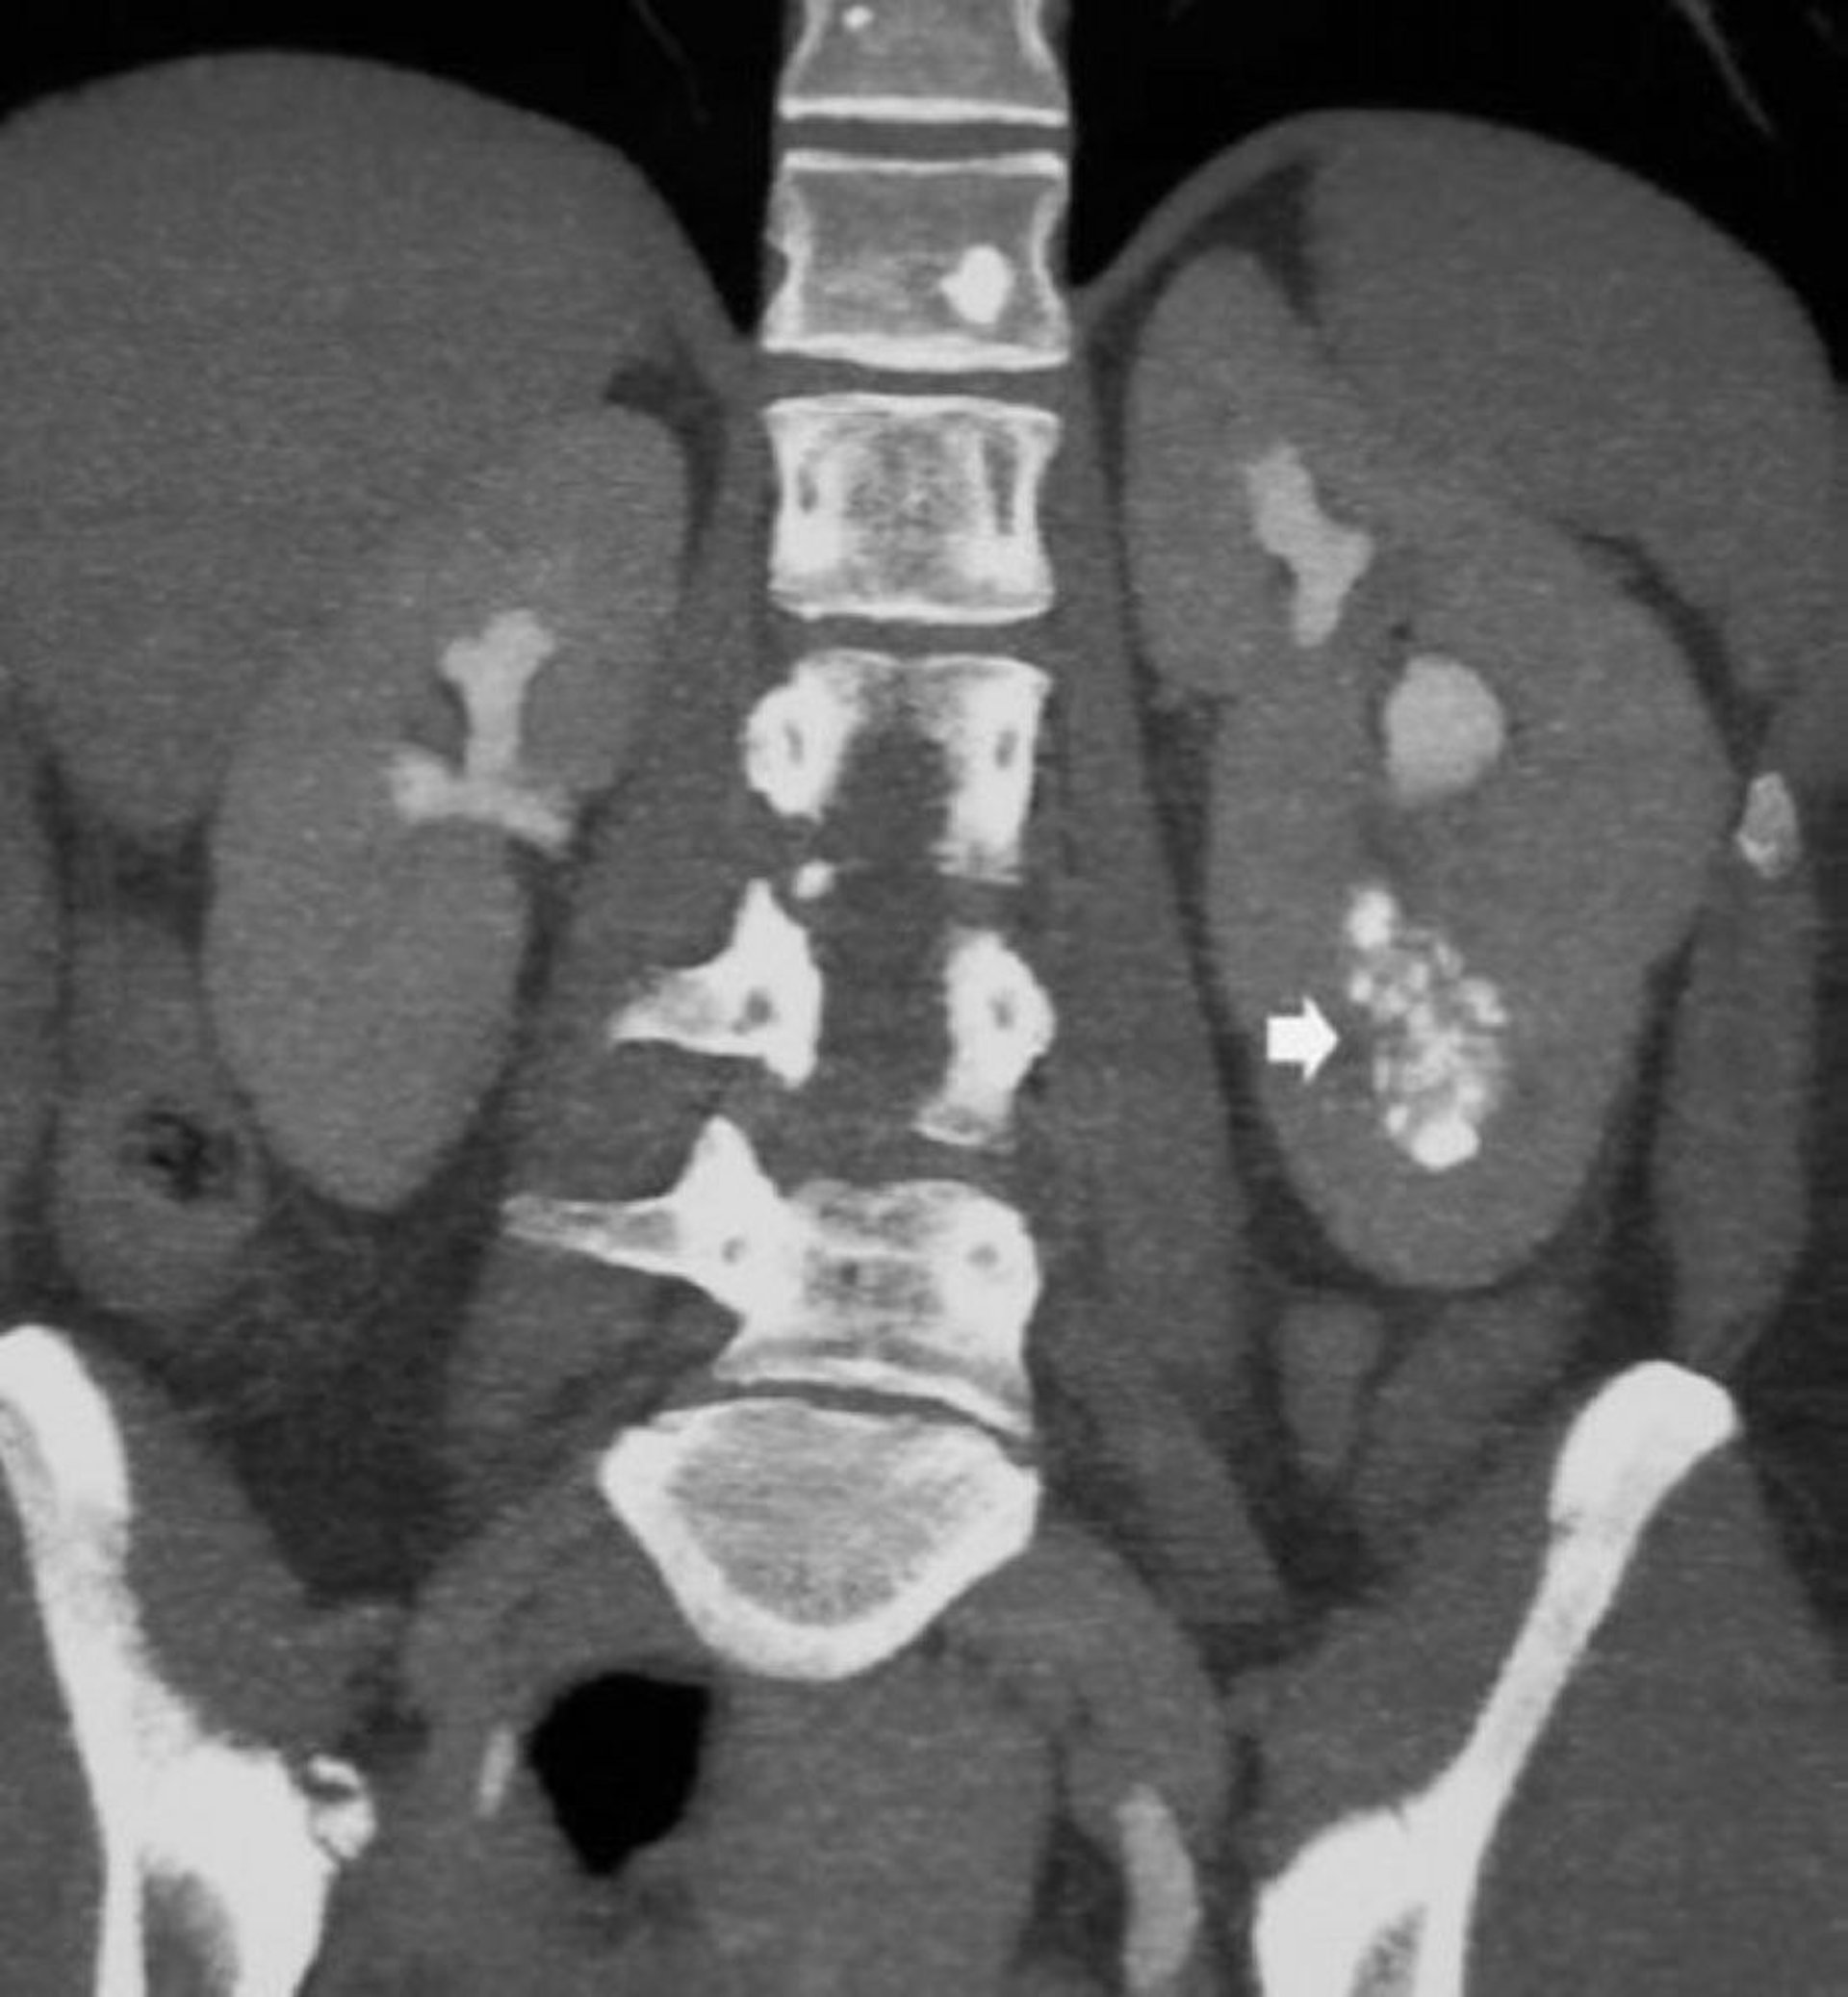

TC coronale senza contrasto che mostra nefrocalcinosi midollare

Questa immagine mostra nefrocalcinosi midollare e dotti collettori dilatati pieni di contrasto in un paziente con rene a spugna midollare (freccia).